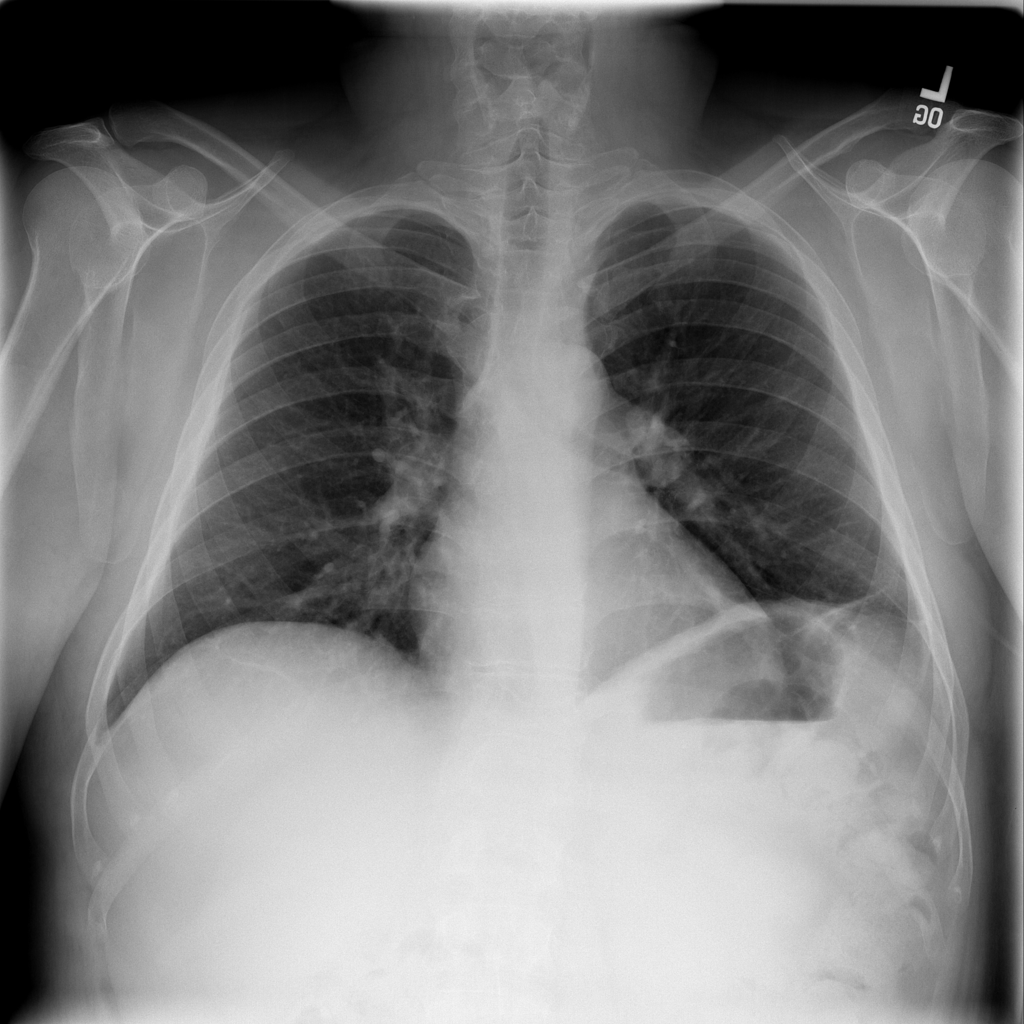

PAT-86C8 · IMG-006Atelectasis

PAT-86C8 · IMG-006

PA